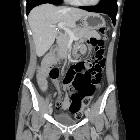

CT

Features are those of a pelvic small bowel closed-loop obstruction:

- small bowel dilatation

- double transition point in pelvic location, lateral to the uterus.

- pelvic free fluid